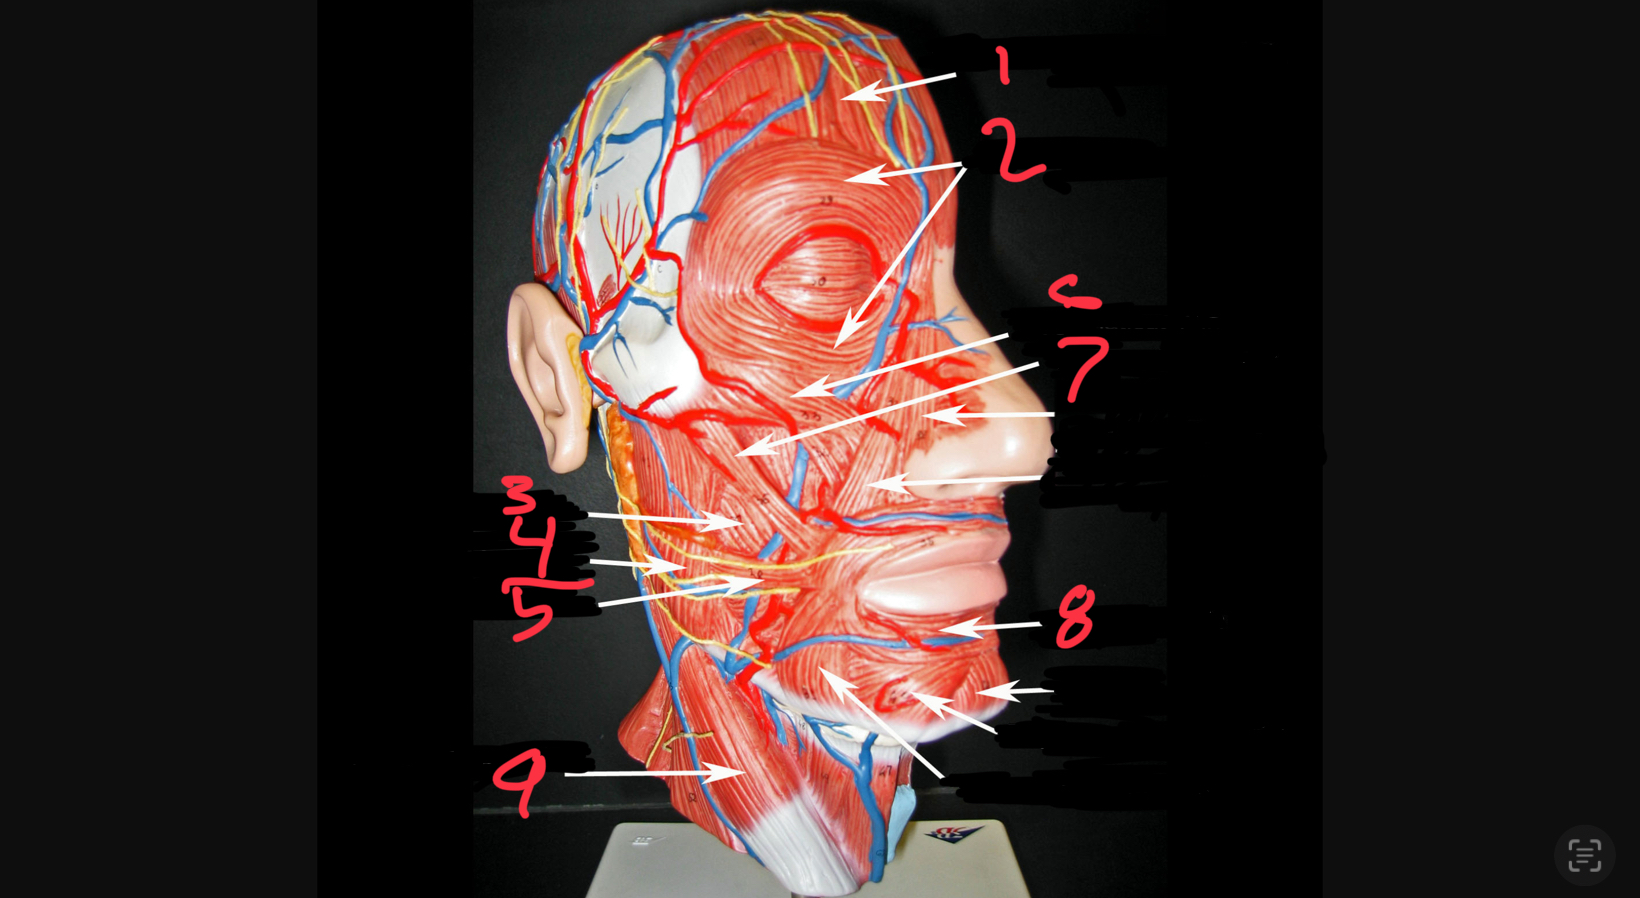

what #1

occipitofrontalis (frontal belly)

what is #2

orbicularis oculi

what is #3

buccinator

what is #4

masseter

what is #5

risorius

what is #6

zygomaticus minor

what is #7

zygomaticus major

what is #8

orbicularis oris

what is #9

sternocleidomastoid